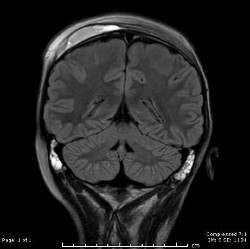

Coupe coronale (plan de droite à gauche) de la colonne cervicale montrant des éclats de vitre dans l’oesophage masqués par le tube endotrachéal (cathéter inséré dans la trachée).